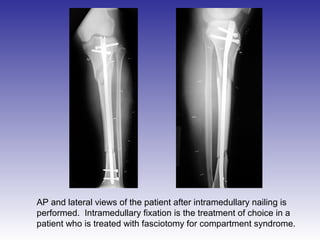

AP and lateral views of the patient after intramedullary nailing is

performed. Intramedullary fixation is the treatment of choice in a

patient who is treated with fasciotomy for compartment syndrome.

AP and lateralviews of the patient after intramedullary nailing is performed. Intramedullary fixation is the treatment of choice in a patient who is treated with fasciotomy for compartment syndrome.